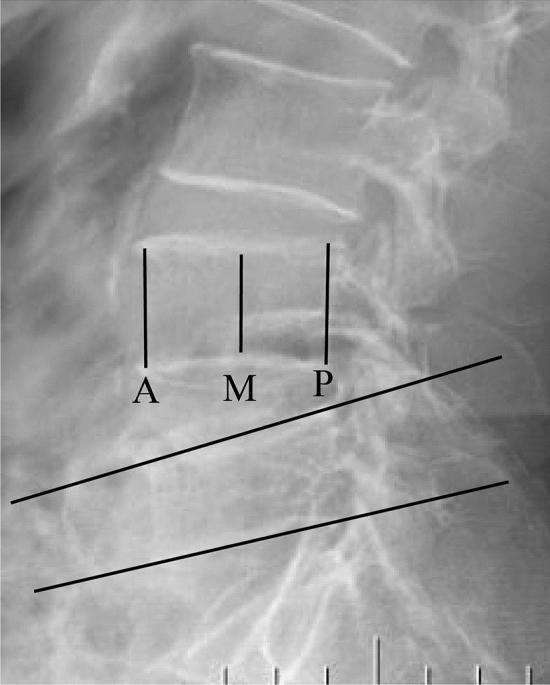

This study introduced a novel point "O" puncture approach for percutaneous kyphoplasty (PKP) in patients with L4 or L5 osteoporotic vertebral compression fracture (OVCF) and evaluated its clinical and radiographic outcomes. Between September 2019 and December 2020, we compared the clinical and radiographic outcomes in 31 cases (36 vertebrae) using the "O" entry point PKP intervention (O-PKP) and 31 cases (37 vertebrae) using transverse the process-pedicle approach PKP intervention (T-PKP). No serious postoperative complications were observed in any of the participants. Only two T-PKP patients experienced intervertebral disc space leakage. Compared with the T-PKP patients, the O-PKP patients showed shorter operative time and fluoroscopy times (P < 0.05), comparable blood loss and cement volume (P > 0.05), improved VAS and ODI scores at the final follow-up (P < 0.05), better increases in the vertebral compression ratio (P < 0.05), comparable Cobb angle (P > 0.05), comparable anteroposterior bone cement distribution, enhanced bilateral bone cement distribution (P < 0.05), and larger sagittal and transverse angles (P < 0.05). Herein, O-PKP was indicated for patients with L4 or L5 OVCF. This puncture approach showed significant advantages over T-PKP not only in terms of pain relief, surgery and fluoroscopy times but also in the puncture angle, vertebral reconstruction, and symmetrical cement distribution.

本研究介绍了一种新型的经皮椎体后凸成形术(PKP)入路点“O”在 L4 或 L5 骨质疏松性椎体压缩性骨折(OVCF)患者中的应用,并评估了其临床和影像学结果。2019 年 9 月至 2020 年 12 月,我们比较了 31 例(36 个椎体)采用“O”入路 PKP 干预(O-PKP)和 31 例(37 个椎体)采用横突-椎弓根入路 PKP 干预(T-PKP)的临床和影像学结果。所有患者均未出现严重的术后并发症。仅有 2 例 T-PKP 患者出现椎间盘空间渗漏。与 T-PKP 患者相比,O-PKP 患者的手术时间和透视时间更短(P<0.05),术中出血量和骨水泥体积相当(P>0.05),末次随访时 VAS 和 ODI 评分改善(P<0.05),椎体压缩率增加更明显(P<0.05),Cobb 角相当(P>0.05),骨水泥的前、后分布相当,双侧骨水泥分布增强(P<0.05),矢状位和横位角度更大(P<0.05)。因此,O-PKP 适用于 L4 或 L5 OVCF 患者。与 T-PKP 相比,这种穿刺方法不仅在缓解疼痛、手术和透视时间方面具有显著优势,而且在穿刺角度、椎体重建和双侧骨水泥分布方面也具有显著优势。